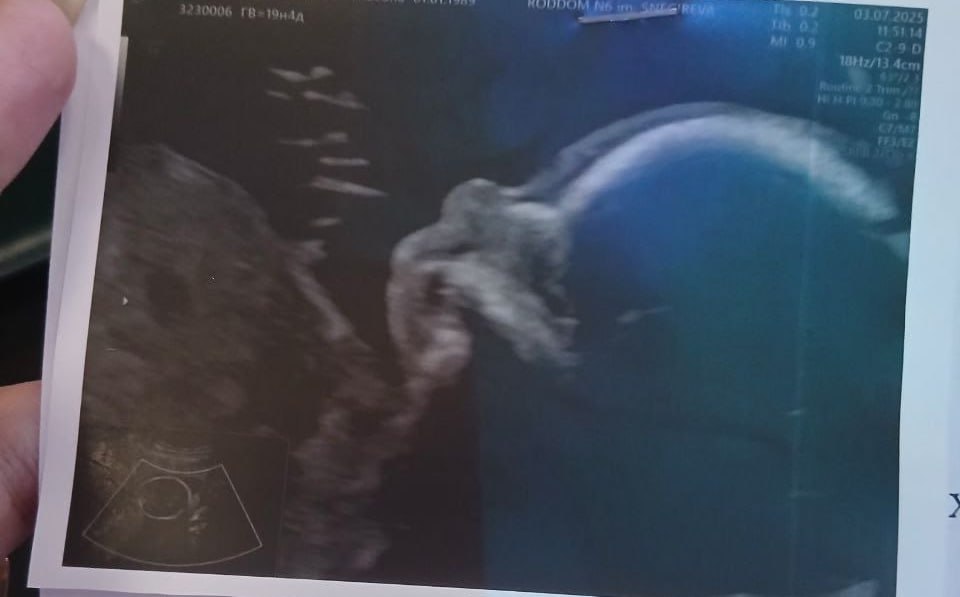

«Вчера все точно подтвердили, что будет сын. Я даже прослезилась. Я изначально знала. Впервые в жизни, я поняла, что готова вырастить мужчину. Я знаю, что это особенный ребенок. У него большое будущее»,

— писала Анастасия еще в июле.